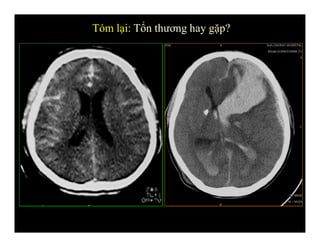

Tóm lại: Tổn thương hay gặp?